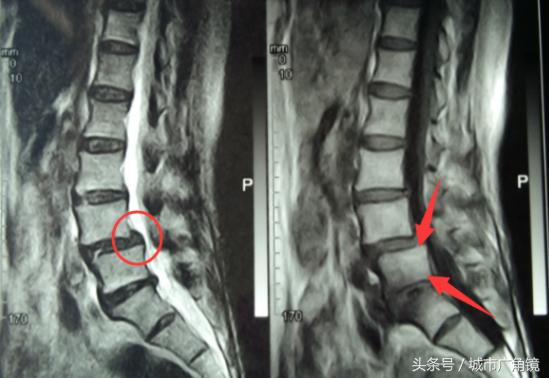

经诊断,陈大娘除患有腰椎间盘突出症(腰4-5)外,还存在腰椎管狭窄和腰椎体滑脱问题。“如果腰椎体稳定,可以考虑微创治疗,但目前患者的腰椎体已出现滑脱。故,钉棒系统内固定是较佳选择。”该院医生解释道,腰椎体滑脱多发于50—60岁的老年人,主要由椎间盘退行性变,关节突关节紊乱,周围韧带松弛,椎间隙不稳等引起。特别是患者的身体在做前屈后伸动作时,椎体就会前后移动,进而刺激神经,下肢出现麻木。他补充,患者步行200米后需休息后方能继续行走,这是腰椎管狭窄的典型症状:间歇性跛行。

笔者了解到,该技术是目前治疗腰椎间盘突出症合并腰椎管狭窄以及腰椎体滑脱(不稳)的一种比较公认的手术方式,在临床上已得到广泛的应用,安全性高,疗效确切。简单来说,就是将病灶部位的椎间盘摘除,同时处理腰椎管狭窄,彻底解除它对相邻神经根的刺激和压迫,以此达到缓解腰腿疼痛等目的。

另外,对于椎间盘摘除后两个椎体间留下的空隙,医生则会植入Cage假体进行代替,起到原有椎间盘连接上下椎体、吸收震荡、分解压力等方面的功能。换言之,植入Cage就等同于“长出了一个新椎间盘。”

由于Cage植入前在其内部填充了适量自体骨骼,所以术后它会与上下相邻的两个椎体完美融合,这不仅符合生物学特性、无排斥,且椎体的稳定性也较佳。而钉棒系统,则是在此基础上对滑脱椎体进行支撑固定。